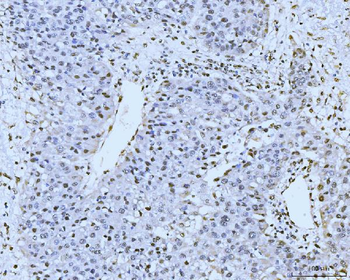

- PPM1D Rabbit Polyclonal Antibody [orb704535]Featured

IF, IHC-Fr, IHC-P

Human, Mouse, Rat

Mouse, Rat

Rabbit

Polyclonal

Unconjugated

100 μl, 50 μl, 200 μl - HSC70 Mouse Monoclonal Antibody [orb704174]Featured